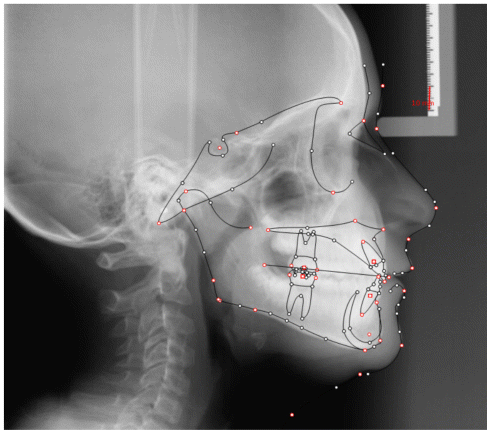

The patient was a growing female child who presented during early mixed dentition with an anterior crossbite associated with a deep overbite and a marked sagittal discrepancy (Figures 12–19). The initial clinical examination revealed a negative overjet, complete anterior deep bite, and a functional Class III occlusal pattern. Extraoral assessment showed a flattened facial profile, while cephalometric analysis confirmed a skeletal imbalance characterized by increased SNA and SNB values, an ANB of 0°, negative Withs appraisal, and significant dentoalveolar compensations, including proclination of both upper and lower incisors (Table 3). The vertical pattern was predominantly hypodivergent, suggesting a high risk of unfavorable mandibular growth progression if left untreated. Given the patient’s young age and growth potential, an early interceptive treatment was planned to use the AMCOP® TC appliance, with the aim of correcting the anterior crossbite, improving neuromuscular balance, and guiding sagittal and vertical development during growth. The appliance was worn nightly and for additional daytime hours, according to patient compliance.

After 18 months of treatment, a clear clinical improvement was observed. Intraoral examination demonstrated complete correction of the anterior crossbite, with establishment of a positive overjet and normalization of the anterior occlusal relationship. The deep bite was reduced, allowing more functional anterior guidance. Occlusal relationships improved toward a stable dental Class I, and the need for excessive dentoalveolar compensation was reduced. Cephalometric reassessment showed an overall improvement in sagittal relationships and incisor inclinations, with a trend toward normalization of the previously altered parameters. These findings indicate that early functional therapy with the AMCOP® TC appliance was effective in intercepting the developing Class III malocclusion, improving occlusal function, and potentially reducing the severity of future skeletal discrepancies (Table 4).